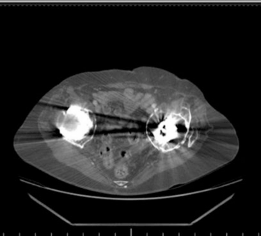

Given the complexity of the defect and the need for meticulous preoperative planning, a

computed tomography (CT) scan with 3D reconstructions

was indispensable.

CT findings:

Confirmed severe Paprosky type IIIb acetabular bone loss, characterized by:

* Complete loss of the superior dome.

* Discontinuity of the anterior and posterior columns in segments.

* A large contained cavitary defect with an uncontained segmental defect superiorly.

* The medial wall was largely intact but severely thinned, with evidence of medial protrusion of the polyethylene liner.

* The femoral head allograft used in the previous revision showed patchy integration with areas of non-union and resorption, failing to provide adequate structural support.

* 3D reconstructions clearly delineated the extent of the superior and posterosuperior wall deficiencies, crucial for planning the appropriate cage and bone graft construct. They also helped to identify the remaining host bone available for screw fixation.